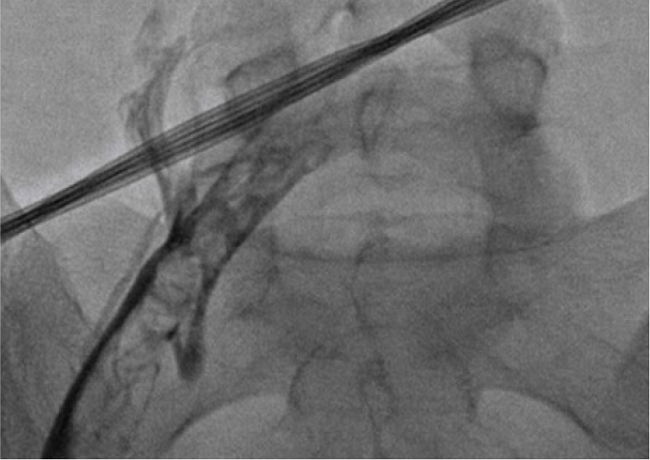

El día 11 del puerperio se decide realizar trombolisis local, la flebografía corrobora trombosis de todo el eje ilio cava izquierdo. Previo consentimiento informado, se decidió recanalizar todo el eje venoso hasta la cava retrohepática y se realizó trombolisis con alteplasa en bolo inicial de 4 mg, con goteo de mantenimiento a razón de 1,5 mg/h.

Durante el procedimiento no fue suspendida la heparina de bajo peso molecular. A las 30 h de la trombolisis presentó sangrado vaginal y frecuencia cardiaca de 91 lpm, tensión arterial de 80/40 mm/ hg, frecuencia respiratoria de 22 rpm y saturación de oxígeno del 92 %. Se diagnosticó choque hipovolémico por hematoma disecante del canal vaginal; se decidió interconsulta con el servicio de hematología, quienes ordenaron realizar transfusión de 2 unidades de glóbulos rojos por caída de hemoglobina mayor a 2 g, reanimación con líquidos cristaloides, empaquetamiento vaginal y colocación de balón de Backri. A las doce horas posteriores, por orden del servicio de hematología, se decide iniciar manejo con enoxaparina a 1 mg/kg cada 12 h, sin nuevos episodios de sangrado. Se eligió la heparina de bajo peso molecular debido a que la incidencia de eventos tromboembólicos venosos recurrentes es menor en personas tratadas con enoxaparina que con heparina no fraccionada. Se llevó a flebografía para definir posibilidad de trombectomía, que se encontró contraindicada por trombos en todo el eje iliaco izquierdo con drenaje por circulación colateral (figura 2), por lo cual se decidió continuar con anticoagulación.